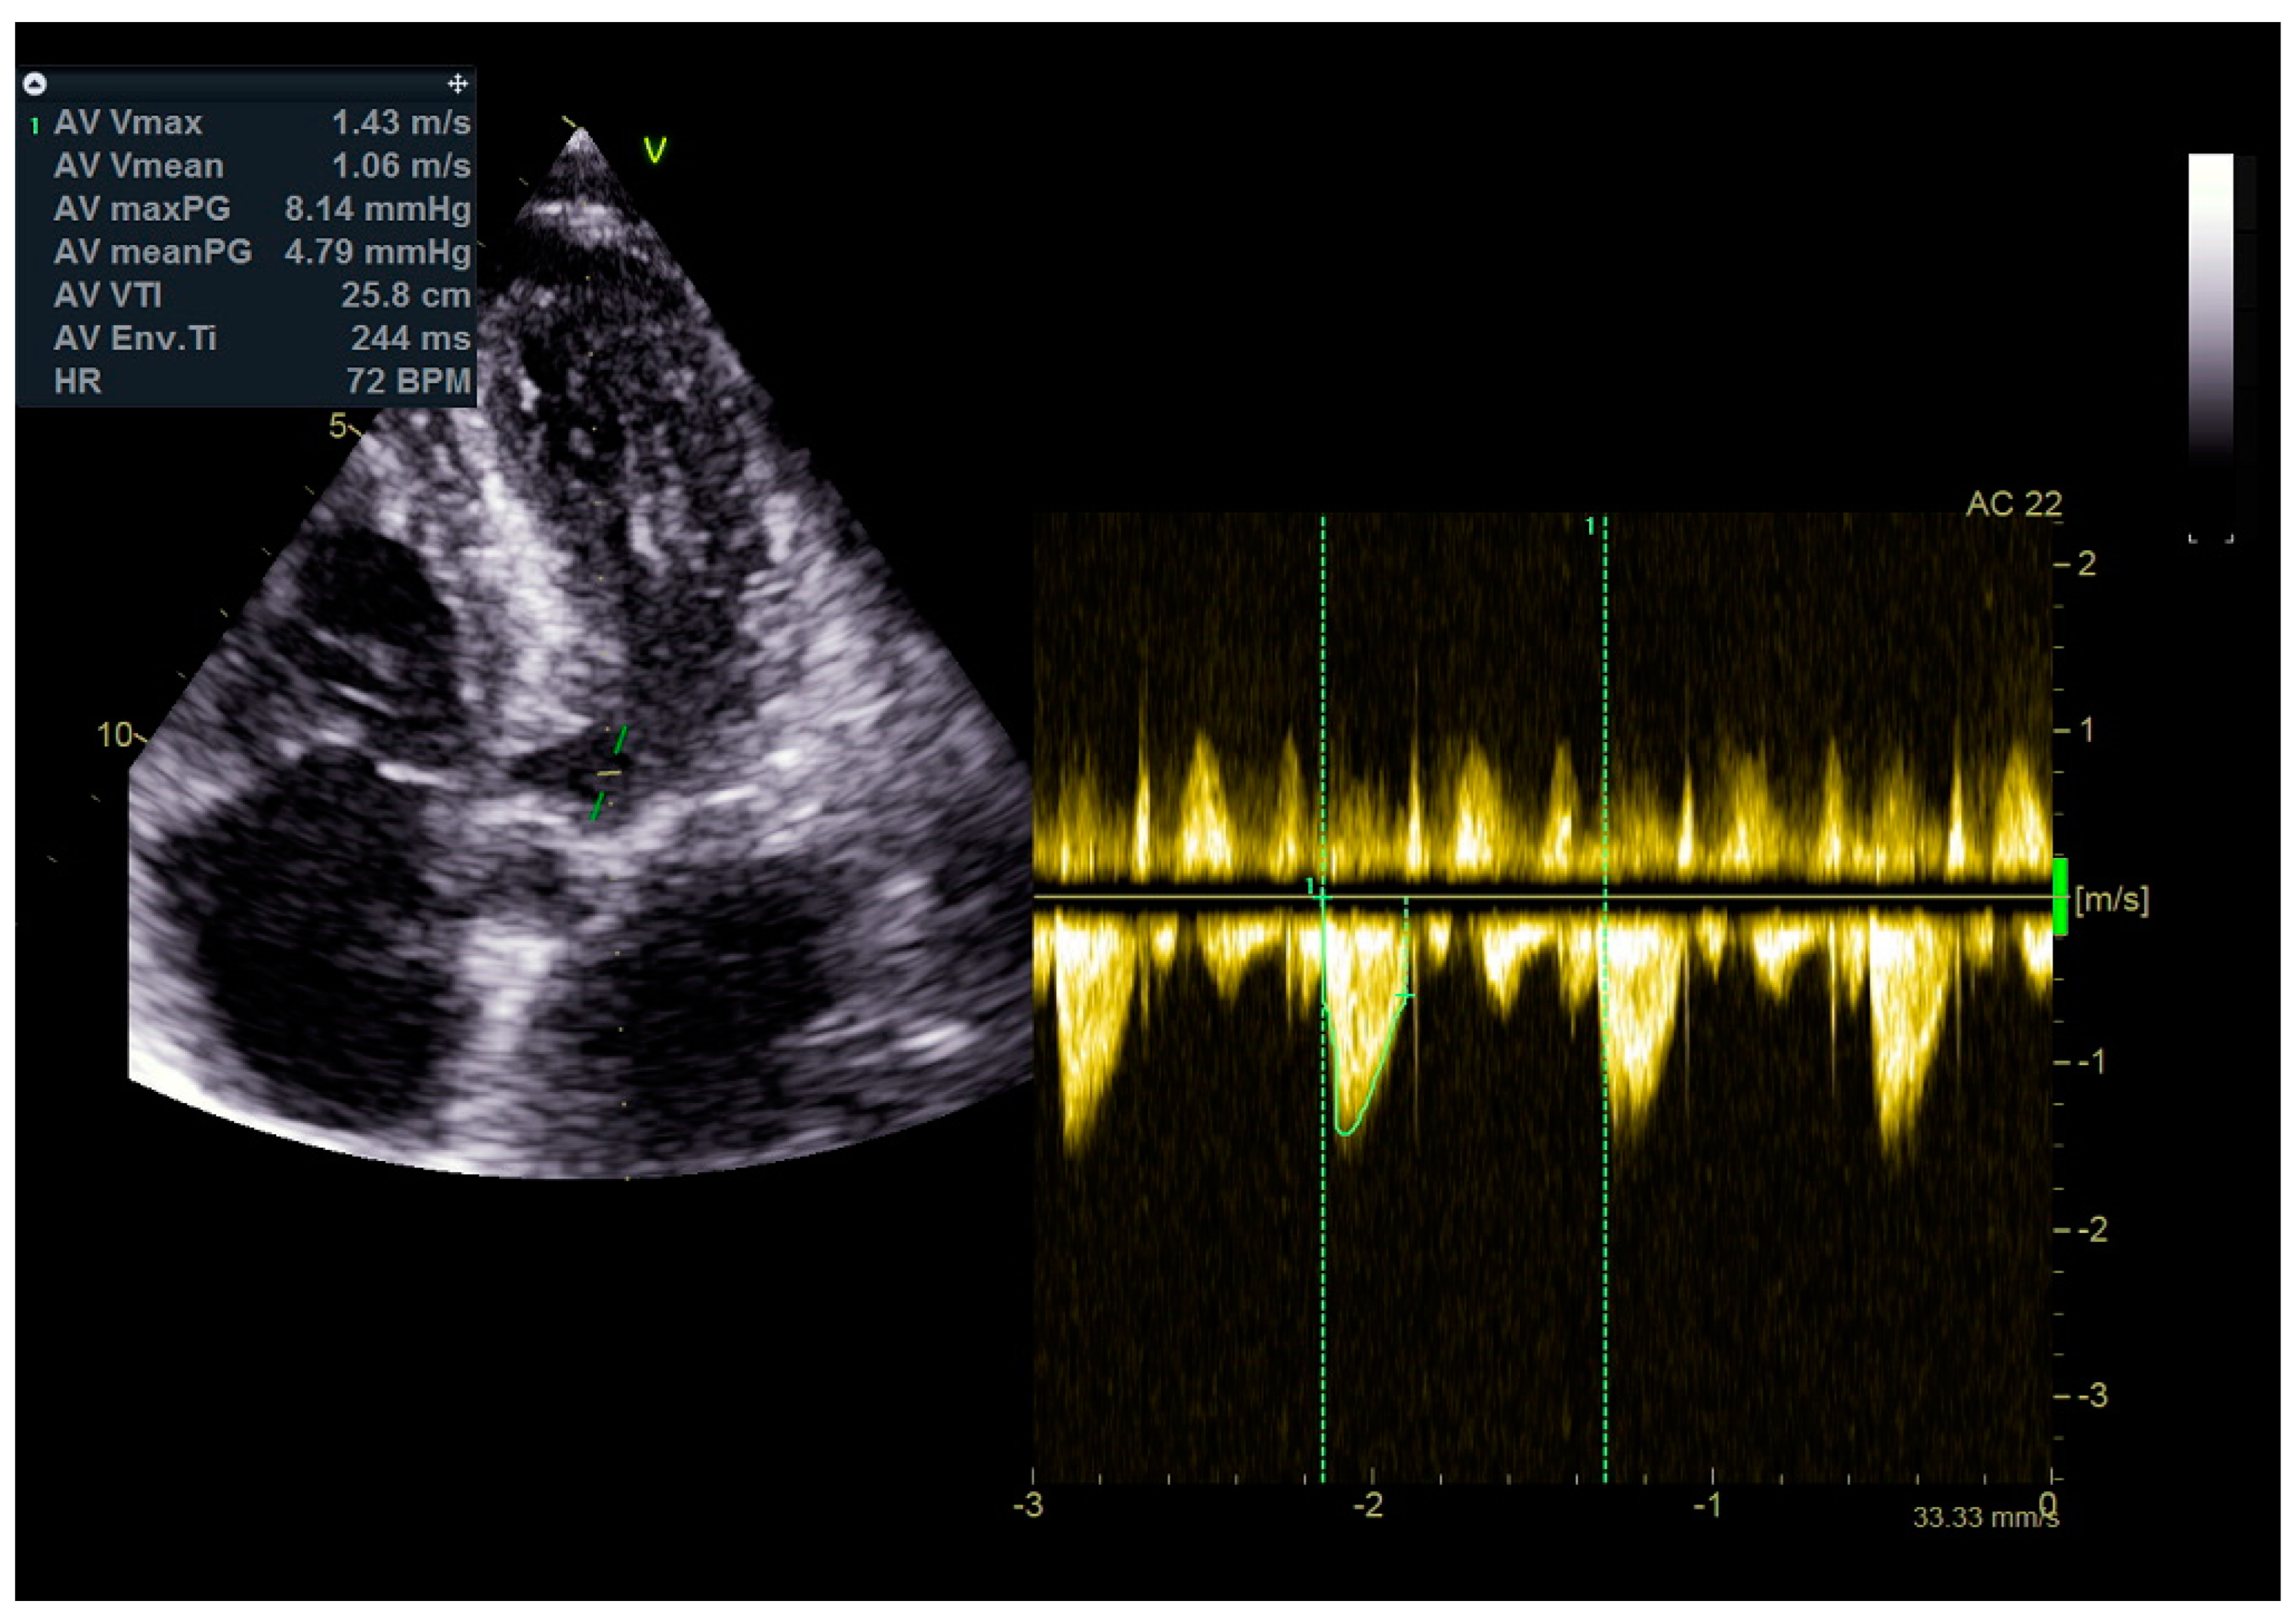

As a result, the patient was referred to a specialized medical institution. Upon admission, the patient was conscious, confused, hypotensive (TA 80/50 mmHg), with a heart rate of about 110/min, and showing clinical signs of hypoperfusion and cardiogenic shock, Killip IV. The medical staff administered sedation, inserted an endotracheal tube, and placed her on invasive mechanical ventilation. The patient was given crystalline solutions, inotrope, and vasopressor medication. An urgent echocardiographic examination was performed due to a rough systolic murmur over the precordium. It revealed akinesia of all medioapical segments of the left ventricle and akinesia basally inferior, where the myocardium was fibrously altered. Other hyperkinetic basal segments formed a dynamic obstruction of the left ventricular outflow tract (LVOTO) with turbulent flow and moderate mitral regurgitation (Figure 2 and Figure 3). The maximum gradient above the LVOT was 160 mmHg (Figure 4). The aortic valve area was 1.8 cm2 (Figure 5). The ejection fraction of the left ventricle (LVEF) was estimated to be 25%. The examination also revealed pericardial effusion with separation between pericardial layers along the right ventricle and atrium of up to 1.2 cm, but without any signs of tamponade.

Figure 5.

Aortic valve area was 1.8 cm2.

Stabilization was achieved gradually, and vasopressor and inotrope support were excluded. By the second day of hospitalization, sedation was stopped, and the patient was alert and responsive. Invasive mechanical ventilation was no longer necessary, and the patient was successfully extubated. On the seventh day of hospitalization, a control echocardiographic examination registered inferior wall akinesia and hypokinesia apically, anteroseptally, inferoseptally, anteriorly, and inferiorly with an estimated LVEF of 52%. No significant gradients were found above the LVOT and there was no pericardial effusion (Figure 11). Mild mitral regurgitation was also registered (Figure 12), but there was no systolic murmur over the precordium.

Figure 11.

No significant gradients were registered above the LVOT, measured by CW Doppler echocardiography.